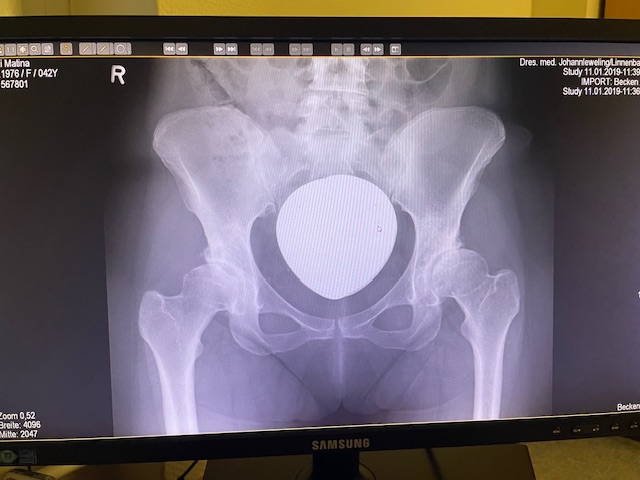

Η ακριβής εφαρμογή του προεγχειρητικού ψηφιακού σχεδιασμού επιβεβαιώθηκε διεγχειρητικά, επιτυγχάνοντας άριστη σταθερότητα της άρθρωσης και πλήρη ισοσκελισμό των κάτω άκρων. Η κινητικότητα ελέγχθηκε σε όλο το εύρος κίνησης, χωρίς σημεία αστάθειας ή πρόσκρουσης.

Το χειρουργείο ολοκληρώθηκε με απόλυτη επιτυχία !!!

Ιδιαίτερα αξιοσημείωτο είναι ότι δεν υπήρξε ουσιαστική απώλεια αίματος, ενώ η ανάρρωση ήταν εντυπωσιακά ταχεία, χωρίς ανάγκη ισχυρής αναλγησίας. Από το πρώτο 24ωρο μπορούσε να αυτοεξυπηρετηθεί, να σταθεί και να κινηθεί με σταθερότητα, ακολουθώντας τις οδηγίες του φυσικοθεραπευτή. Η ασθενής εξήλθε από το νοσοκομείο την τέταρτη μετεγχειρητική ημέρα, χωρίς πόνο και με πλήρη λειτουργικότητα του ισχίου.